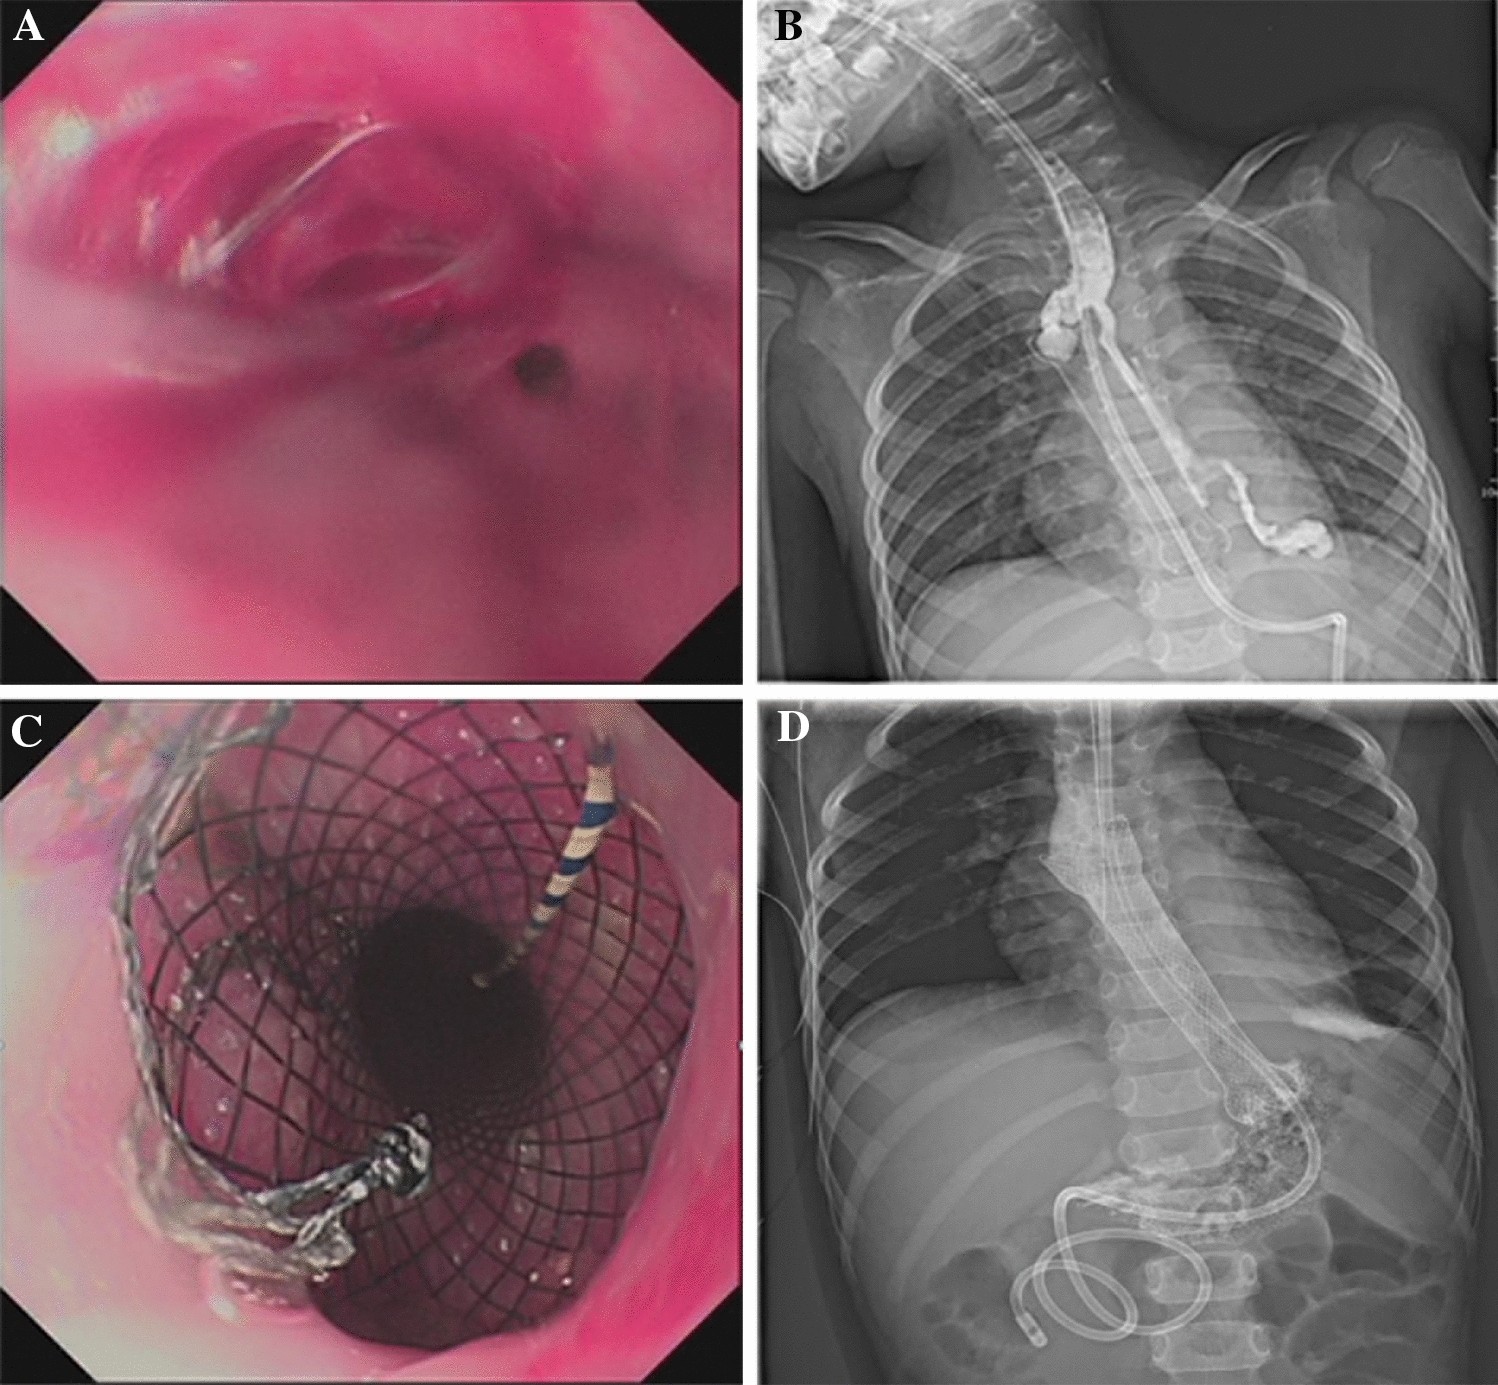

Figure 5

Stent placement in a patient with an EBD-induced esophageal perforation (case 14). (A) Esophageal perforation secondary to endoscopic balloon dilatation, the upper oral mucosa of the stricture was torn and bleeding; (B) Stent malapposition occurred 5 days after the first stent implantation; upper gastrointestinal tract radiography revealed that contrast medium infiltrated the mediastinum; (C) The original esophageal stent was replaced by a redesigned stent with larger upper bell mouth; (D) After the second esophageal stent was placed, upper gastrointestinal tract radiography revealed that the fistula was plugged, without contrast medium extravasating.